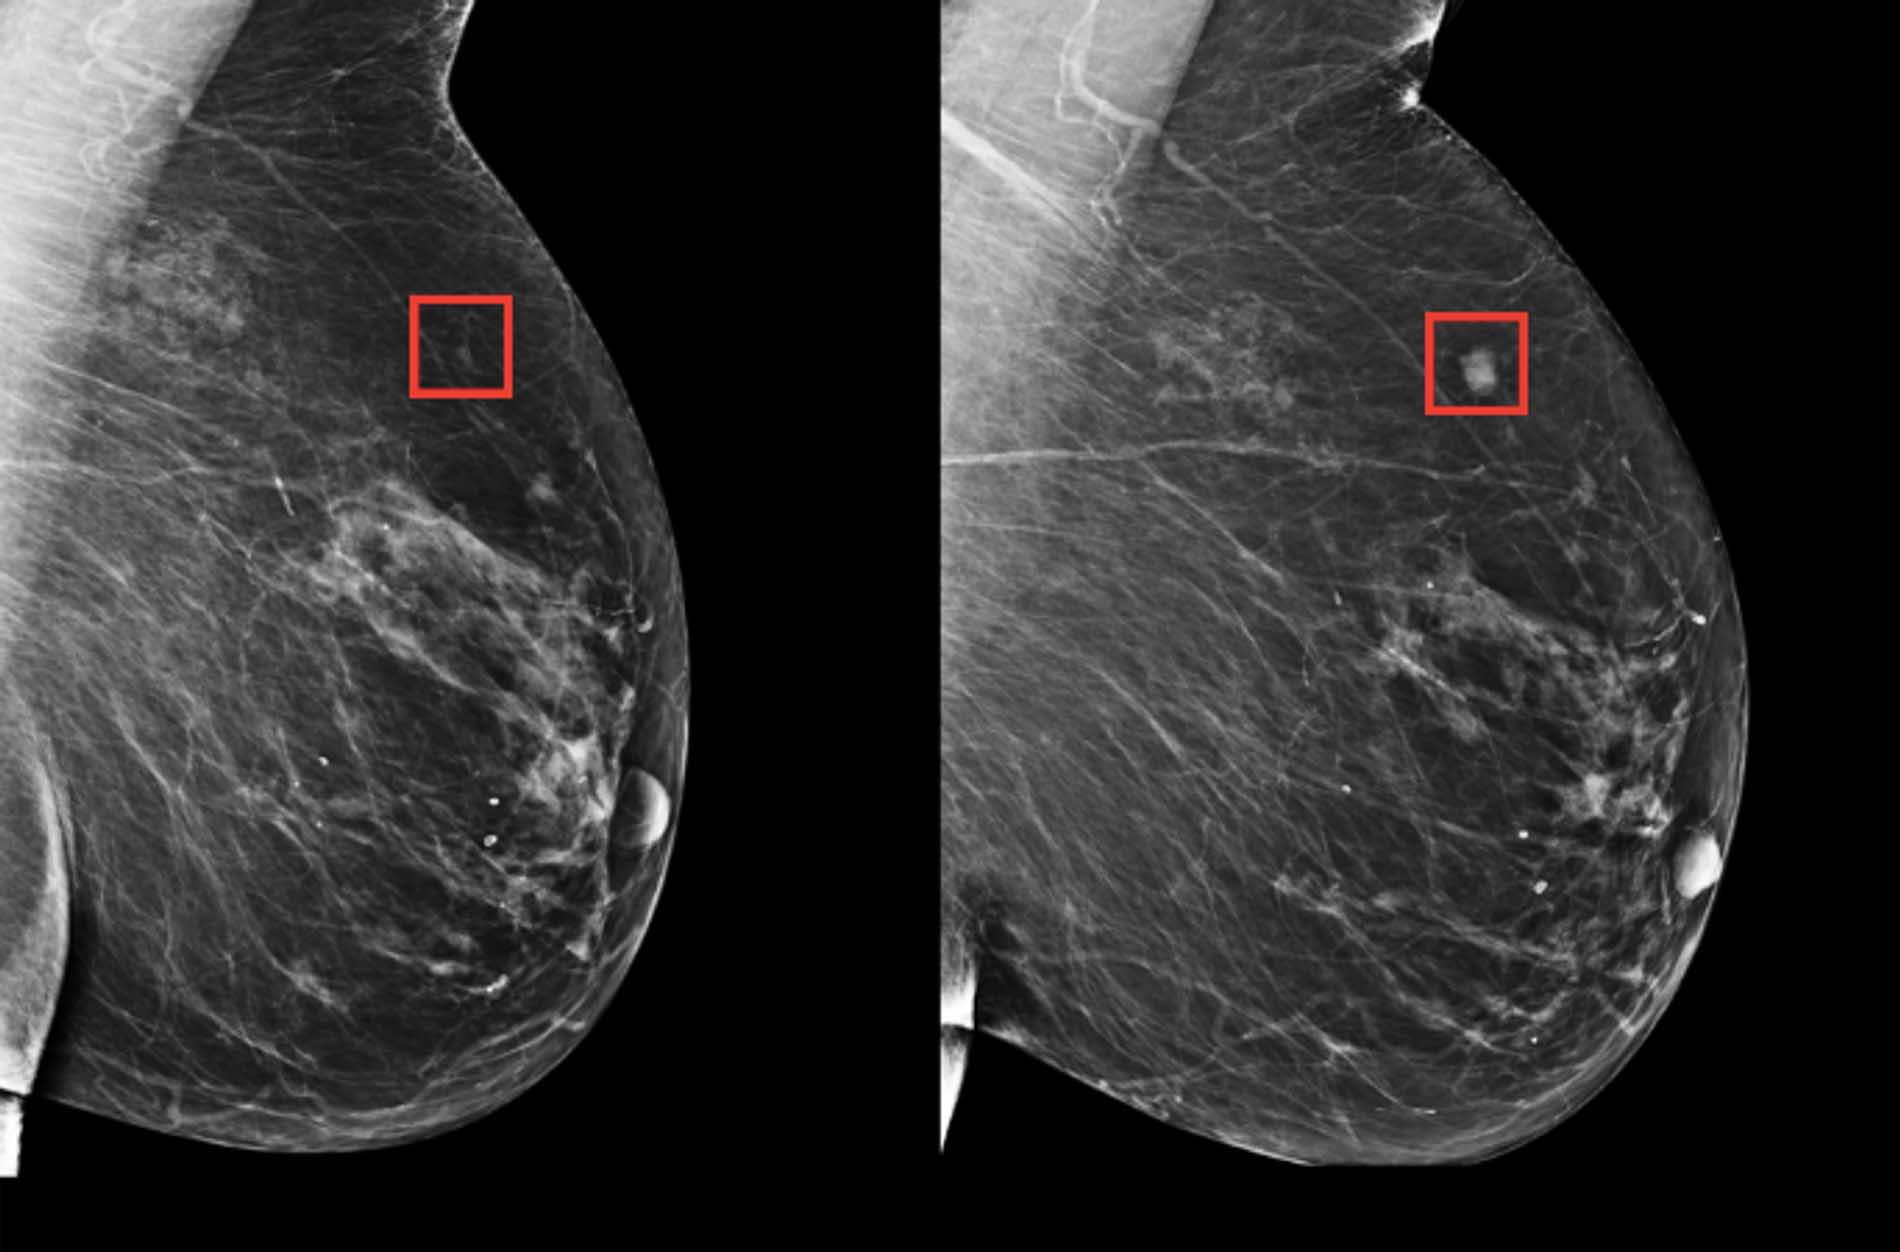

El sistema de IA procesa automáticamente las imágenes de la tomografía computarizada y destaca los posibles signos de cáncer para su posterior evaluación por parte de los médicos.